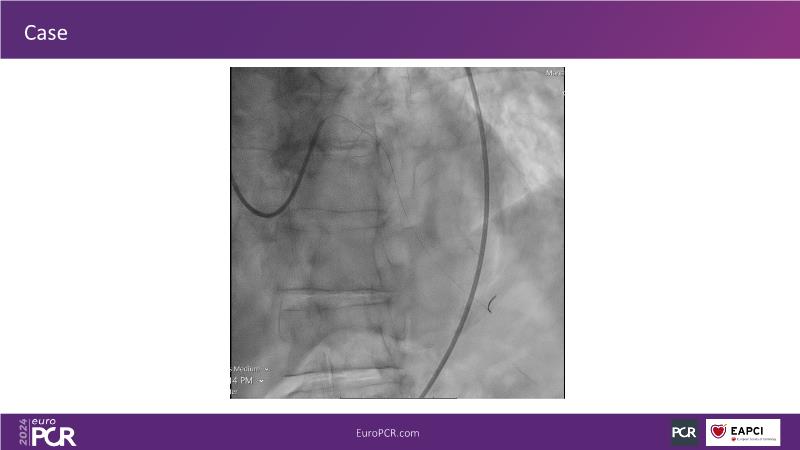

Tune into this 2024 session for insights into the latest ESC guidelines, strategies to prevent and treat no reflow, and an examination of trials like TASTE, TAPAS, and TOTAL on coronary thrombus management. Explore also the outcomes of the CHEETAH study, pondering a potential paradigm shift, and delve into a case study on thrombus removal in a patient with high thrombus burden.